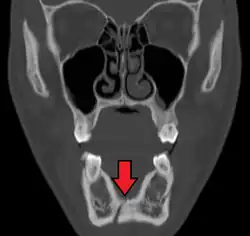

Plain film radiography

Traditionally, plain films of the mandible would be exposed but had lower sensitivity and specificity owing to overlap of structures. Views included AP (for parasymphsis), lateral oblique (body, ramus, angle, coronoid process) and Towne's (condyle) views. Condylar fractures can be especially difficult to identify, depending on the direction of condylar displacement or dislocation so multiple views of it are usually examined with two views at perpendicular angles.[11]

Panoramic radiography

Panoramic radiographs are tomograms where the mandible is in the focal trough and show a flat image of the mandible. Because the curve of the mandible appears in a 2-dimensional image, fractures are easier to spot leading to an accuracy similar to CT except in the condyle region. In addition, broken, missing or malaligned teeth can often be appreciated on a panoramic image which is frequently lost in plain films. Medial/lateral displacement of the fracture segments and especially the condyle are difficult to gauge so the view is sometimes augmented with plain film radiography or computed tomography for more complex mandible fractures.

Computed tomography

Computed tomography is the most sensitive and specific of the imaging techniques. The facial bones can be visualized as slices through the skeletal in either the axial, coronal or sagittal planes. Images can be reconstructed into a 3-dimensional view, to give a better sense of the displacement of various fragments. 3D reconstruction, however, can mask smaller fractures owing to volume averaging, scatter artifact and surrounding structures simply blocking the view of underlying areas.

Research has shown that panoramic radiography is similar to computed tomography in its diagnostic accuracy for mandible fractures and both are more accurate than plain film radiograph.[12] The indications to use CT for mandible fracture vary by region, but it does not seem to add to diagnosis or treatment planning except for comminuted or avulsive type fractures,[13] although, there is better clinician agreement on the location and absence of fractures with CT compared to panoramic radiography.[14]

Towne's view of a bilateral condyle fracture. White arrow is a fracture on the neck of the condyle. Black arrow shows the condyle pulled to the medial. The same injury can be seen on the opposite side